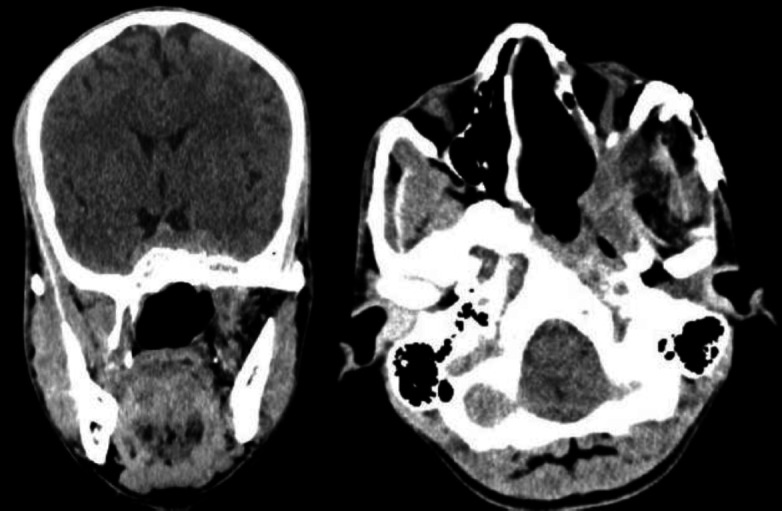

Introduction: In around 10-20% of angiofibroma cases, the tumor penetrates the skull base to involve intracranial structures, posing difficulty in treating them surgically. Today, advancement in skull base surgery has brought about a paradigm shift, and extensive angiofibroma tumors with intracranial extension are approached surgically today with minimal morbidity.

Materials and methods: This study was a retrospective analysis of angiofibroma with significant intracranial extension Radkowski staging IIIb from 2011 to 2021 who came to our center. There were seven children of angiofibroma with significant intracranial extension Radkowski staging IIIb, out of whom, four patients had undergone surgical resection at our center. Three patients underwent surgery by pre-auricular lateral subtemporal approach and one patient by maxillary swing approach. Preoperative embolization was done in all the patients one day before the day of operation.

Results: Gross total removal of the tumor was achieved in all three patients who had undergone pre-auricular lateral subtemporal approach with no permanent complication. All three patients had a minimum follow-up of one year with no recurrence.

Conclusion: The pre-auricular lateral subtemporal approach provides the shortest shallow route to the affected skull base with direct visualization of the tumor base. Hence recommended for angiofibroma with Radkowski staging IIIb.